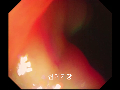

최근 글위소매절제술 전후 비만 .. (0) [인천, 고도비만수술/위.. (0) 고도비만수술의 대세 위소.. (0) 위밴드수술에서 위소매절제.. (0) 위소매절제술 후 감량 (.. (0) 2019년 3월 진료안내.. (2) 봄이 오는 길목에서.. .. (0) 유동식에서 죽식으로 이행.. (0) 위소매절제술 후 유동식 (0) 2019년 2월 외래진료.. (0) |